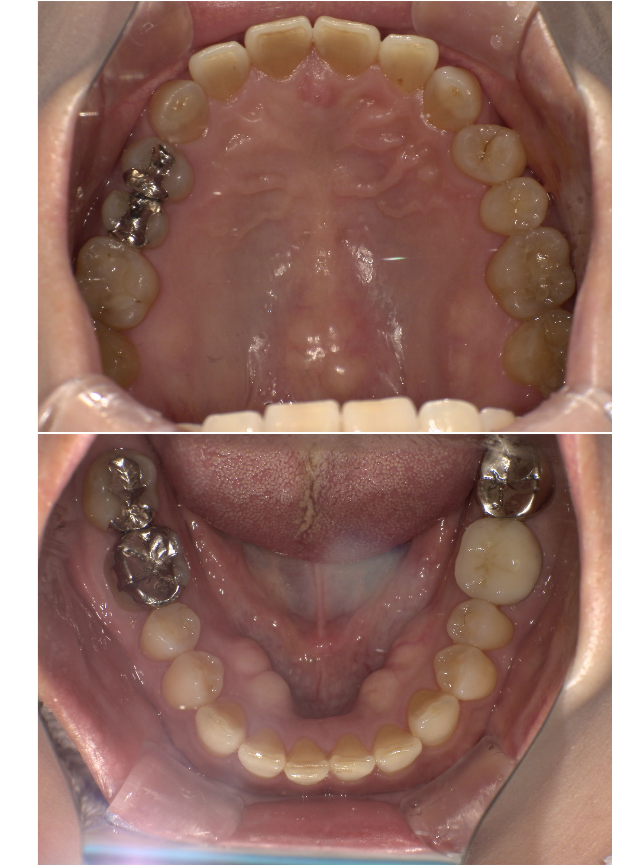

| 治療内容 | 全顎治療 |

| 主訴 | 他院で下の前歯削られた。銀歯を白くしたい。入れ歯の針金見えなくしたい |

| 診断 | 臼歯部欠損による咀嚼障害 |

| 治療期間 | 1年1ヶ月 |

| 治療費用 | 補綴費用ジルコニアクラウン¥120,000×18本+金属義歯¥500,000=¥2,660,000+税 |

| 院長コメント | 奥様のご紹介で来られた60代男性の方です。奥様と同様でとても温和でやさしい方でした。聞こえの困難がある方だったので、すべて筆談で致しました。患者様の希望を踏まえた治療計画はもちろんの事、「どうしてその治療が必要なのか」「治療を選択する際のメリット・デメリット」を丁寧にお伝えし、数回コンサルティングを繰り返し、納得していただいた上で進めていきました。かみ合わせがずれていた可能性があったのでスプリントをほぼ24時間1か月ほど装着してもらい、顎の楽な位置を確かめると同時にすり減った分の歯を補う高さを仮決定しました。そののち精密仮歯と仮の入れ歯を作製し、2か月様子を診ました。全体的な微調整を行った後最終的な補綴物に置き換えていきました。患者様は①歯の長さが適切になったこと②銀歯が白くなったこと③長持ちする治療を受けられたこと④針金が見えなくなったこと、大変喜ばれました。3カ月に一度のペースでメインテナンスに通っていただいております。 |